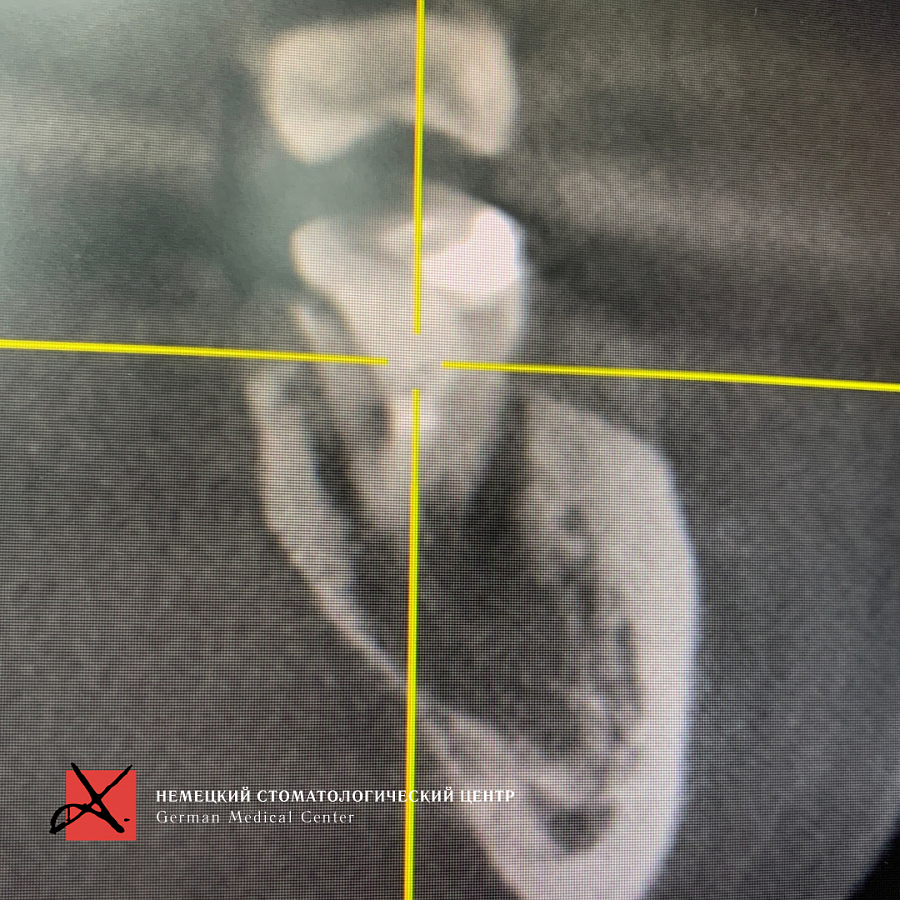

Через 4 месяца проведена установка имплантата. Вокруг имплантата видна успешно зажившая кость, а также видно полноценное отверстие нижнечелюстного канала. Прогнозы благоприятны.